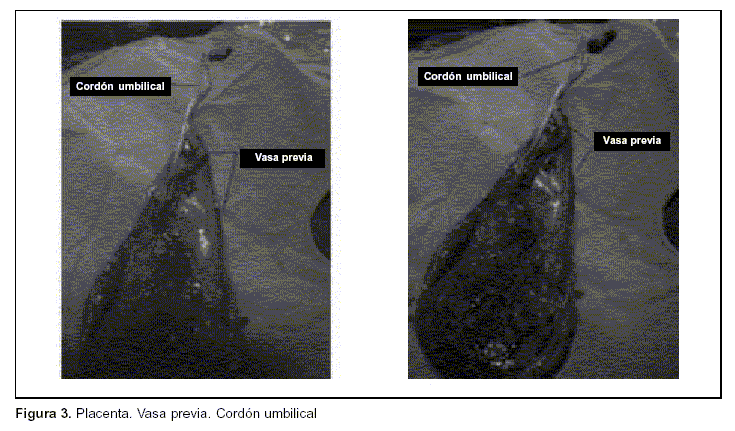

No hay casos de VP publicados en Uruguay. El objetivo de los autores es la comunicación de un caso clínico en el que no se realizó diagnóstico prenatal, pero con resultados perinatales óptimos debido a la vía de finalización del embarazo elegida. (figura 2) (figura 3)

La cesárea se realizó sin complicaciones médico-quirúrgicas. Se obtuvo un recién nacido vivo, sexo masculino, puntaje de Apgar de 9 al primer minuto y 10 a los 5 minutos. Como hallazgo intraoperatorio se destacó la placenta fúndica normoinserta con VP (sin rotura) tipo I, que fue corroborado en el alumbramiento y por anatomía patológica.